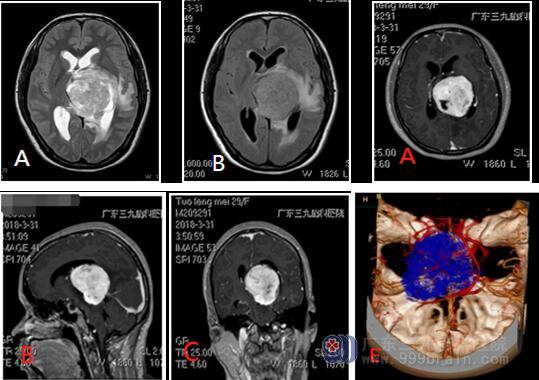

影像学检查 左侧丘脑示一巨大团块状占位性病变,呈欠均匀长T1长T2异常信号影,FLAIR序列呈高信号,FLAIR序列呈稍高信号,其内示多发斑片状更长T1长T2异常信号影,FLAIR序列呈稍低信号,增强后病变大部分呈明显异常强化,内示多发斑片无强化区;病变边界欠清,大小约为5.3cm×5.6cm×5.0cm;周围示片状稍长T1长T2异常信号影,FLAIR序列呈高信号。三脑室明显受压变窄并向右侧偏移。邻近左侧侧脑室受压变窄,余幕上脑室系统扩大。中线结构向右侧偏移。矢状位示垂体变薄,小脑未见异常。右侧上颌窦粘膜稍增厚,余各副鼻窦腔清亮。考虑高级别胶质瘤可能性大。

CTA检查左侧丘脑区域占位病变,其内示多发细小肿瘤血管放射状分布,来源左侧大脑后动脉远端分支参与供血。同时病灶上缘示右侧大脑大静脉及内静脉增粗迂曲,包绕病灶。左侧大脑中动脉分支偏少。左侧椎动脉明显细小。余血管走行规则,管壁未见粥样硬化斑块或钙化斑,未见狭窄、闭塞、畸形血管或局限性囊状增粗影。

注:MRI